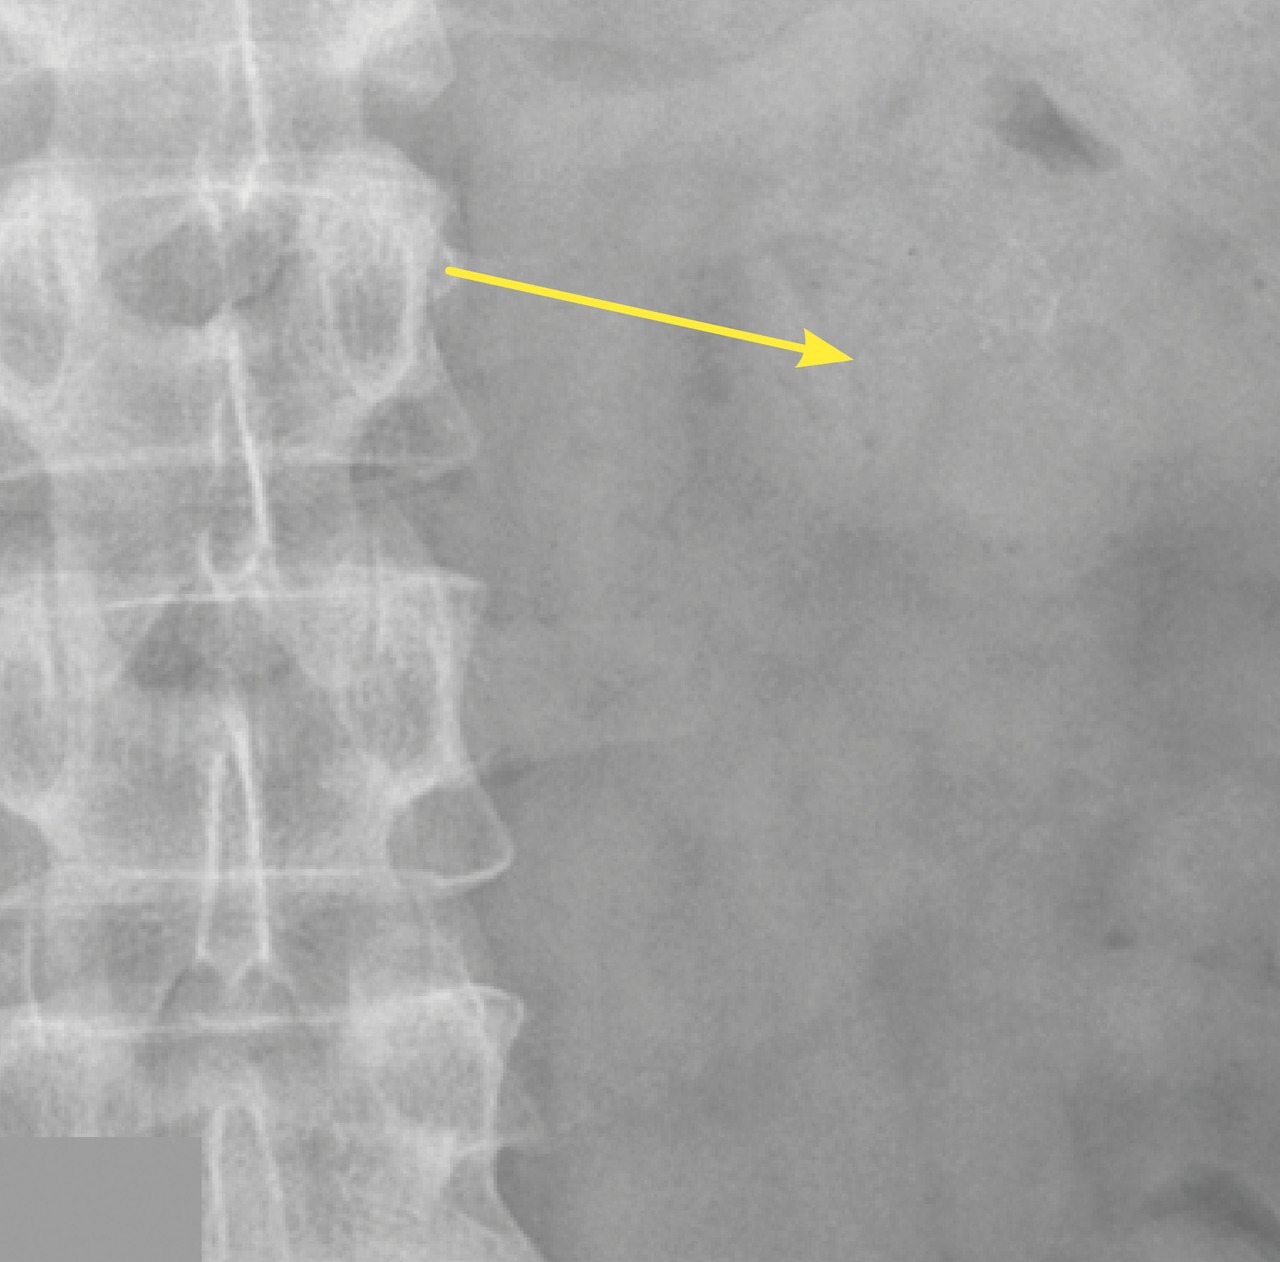

Lors de son hospitalisation, un scanner abdominal permet de localiser avec précision un calcul caliciel rénal radio-opaque gauche de 6 × 8 mm, de faible densité (354 UH), sans dilatation calicielle (fig. 1). En corrélation avec la lecture du scanner, le pourtour du calcul est difficilement visualisé sur la radiographie de l’abdomen sans préparation (fig. 2).